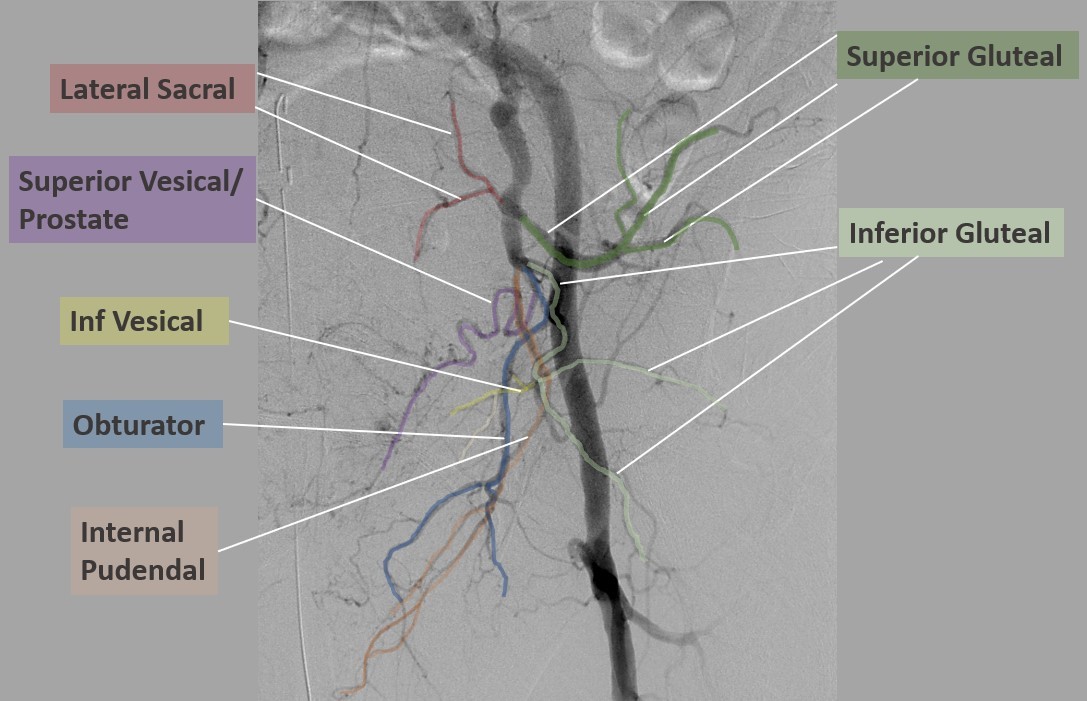

lateral sacral artery

The iliolumbar travels in a cephalad direction which is an identifying feature. It may arise directly off of the internal iliac, rather than a posterior trunk. The lateral sacral artery travels medially and posteriorly in its relationship with the sacrum. There may be more than one lateral sacral branch.

obturator artery

Helpful is the characteristic inverted ‘Y’ at the obturator foramen. This can be a site of bleeding with pelvic trauma. An interesting and important variant is worth mentioning here. The obturator artery can also arise from, or anastomose with, the inferior epigastric artery, running along the posterior aspect of the superior pubic ramus. It can be an unwelcome surprise to a surgeon and can be difficult to control, earning the moniker ‘corona mortise’ or crown of death.